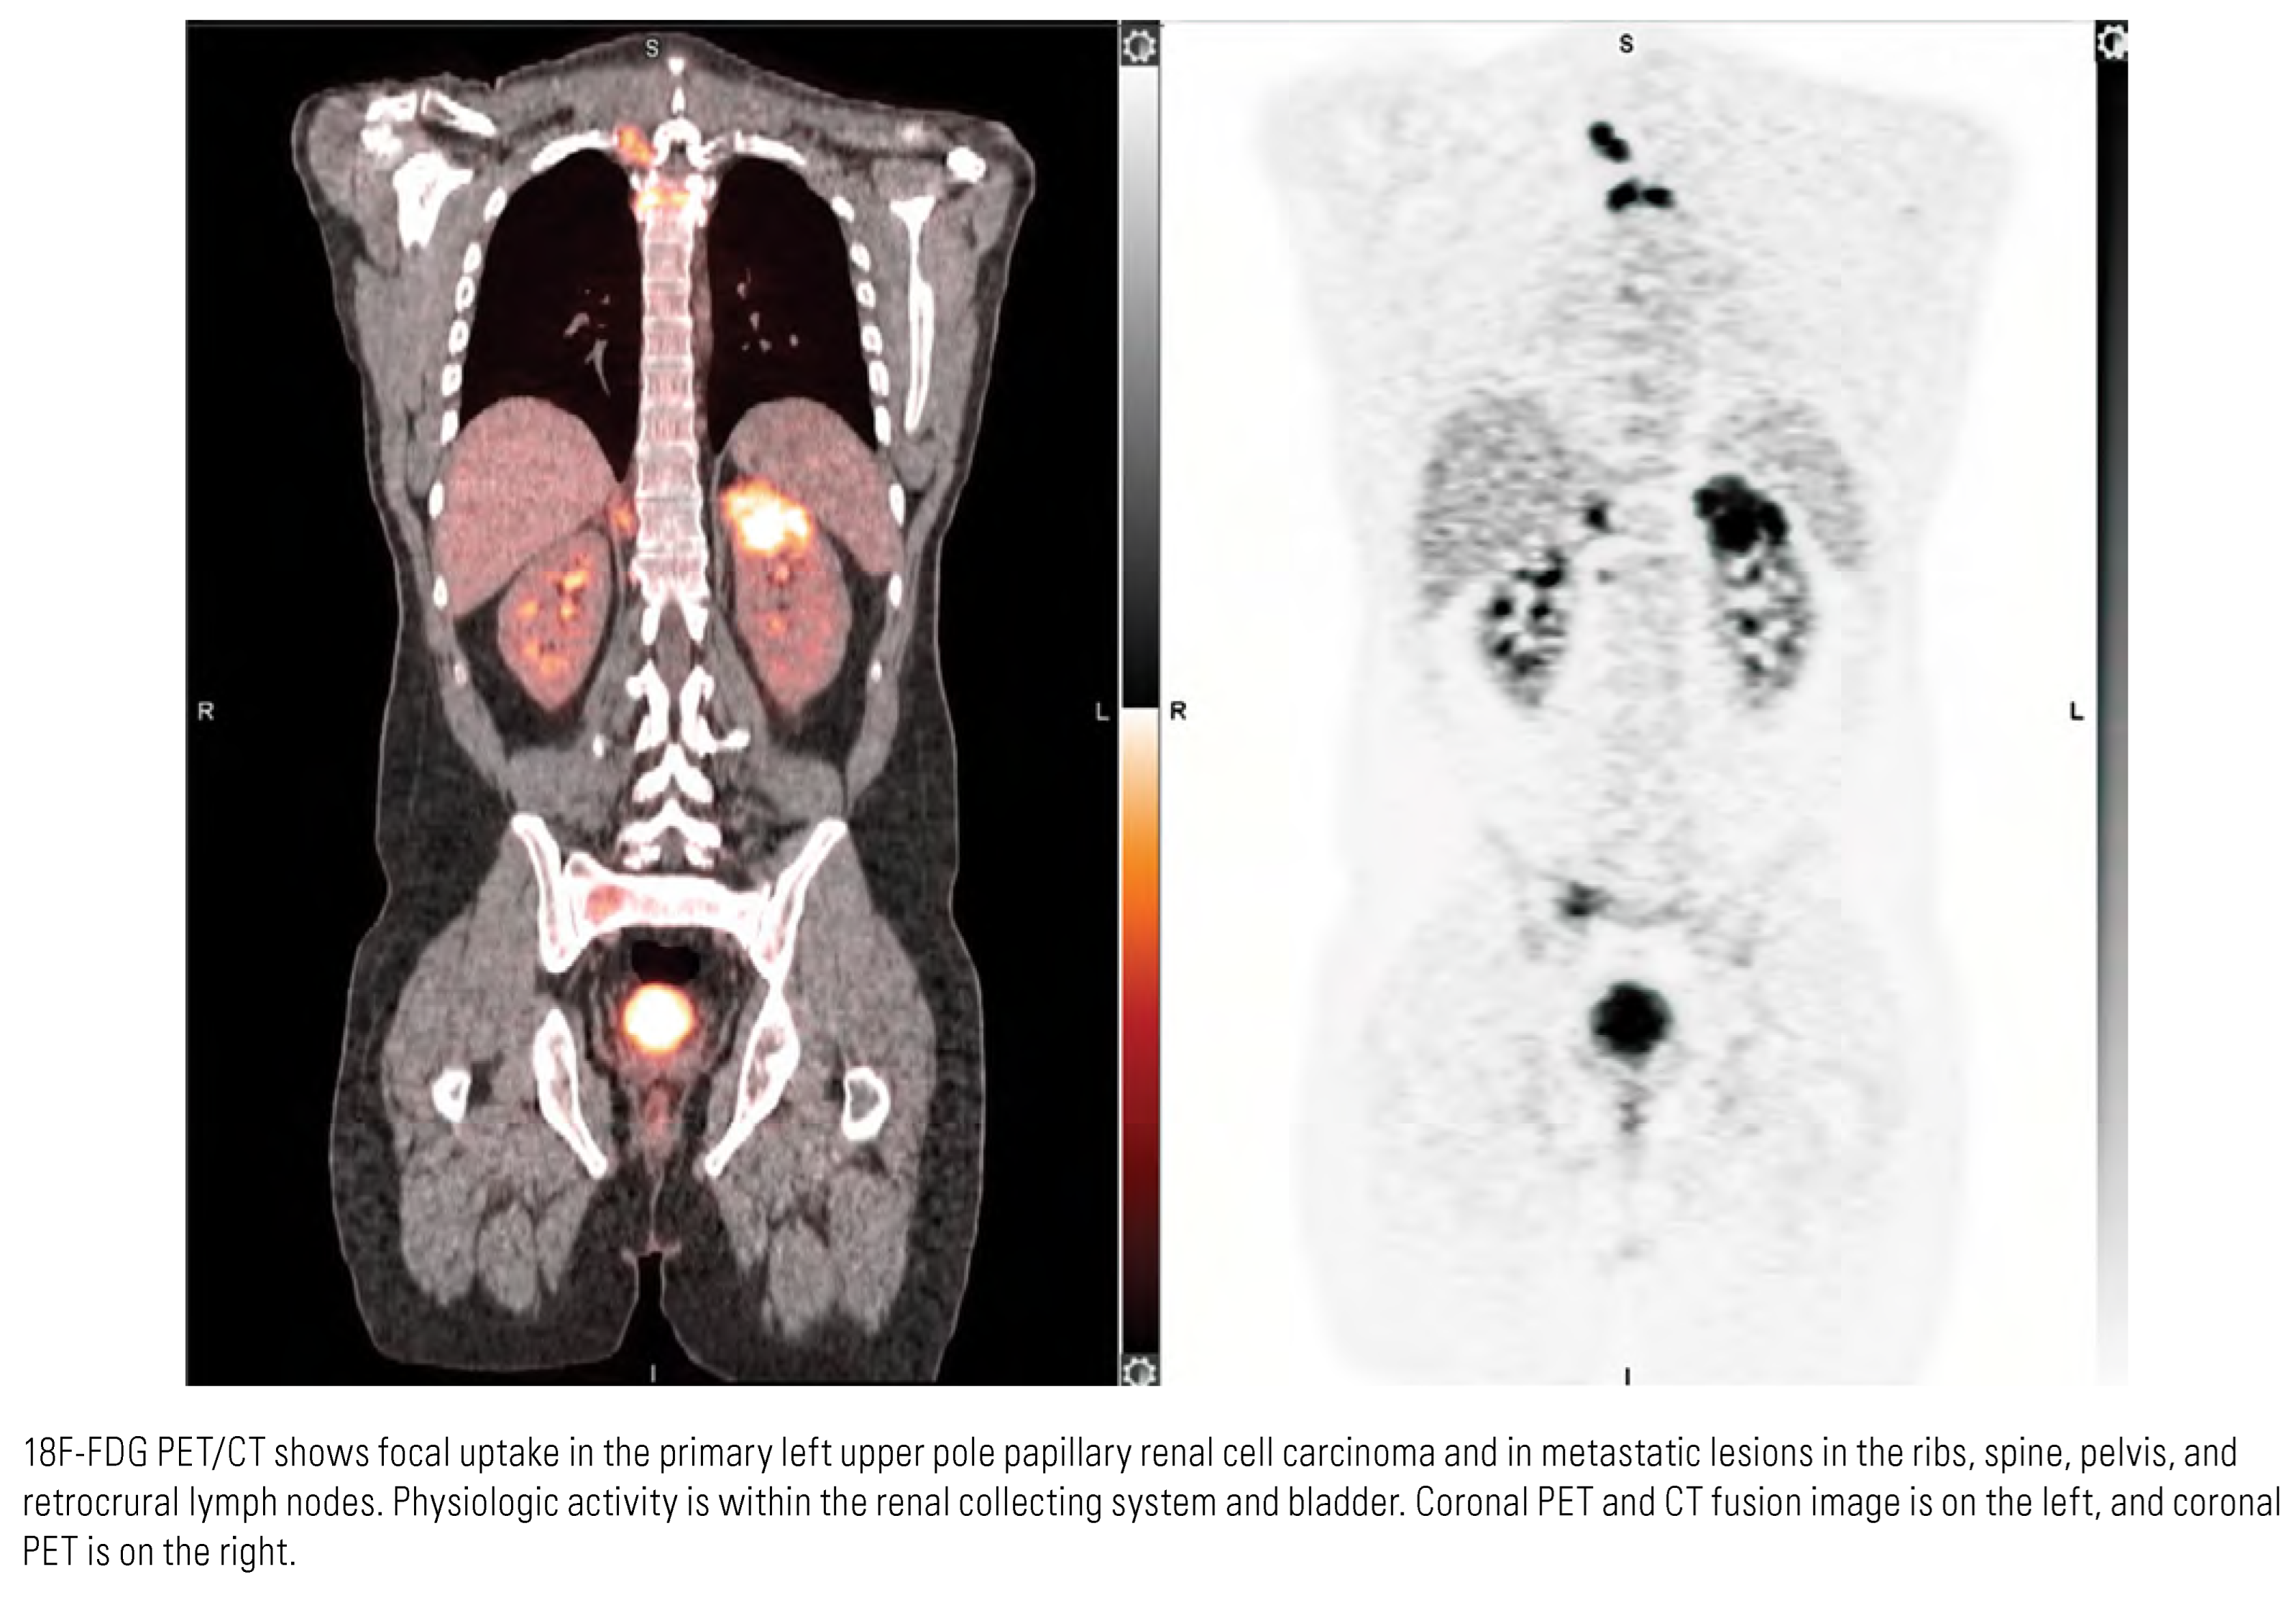

Evaluation of Nodes and Distant Metastases